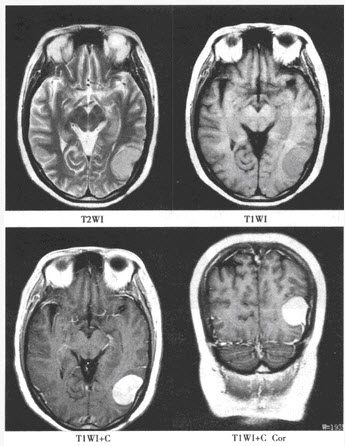

5、单项选择题

患者,女,50岁,因头晕半年来院检查,影像检查如下图。

A.星形细胞瘤

B.少突胶质细胞瘤

C.室管膜瘤

D.脑膜瘤

E.转移瘤

F.脑囊虫病

7、单项选择题

A.脑膜尾征

B.钙化

C.均匀强化

D.发病部位

E.周围水肿明显

F.以上都不是